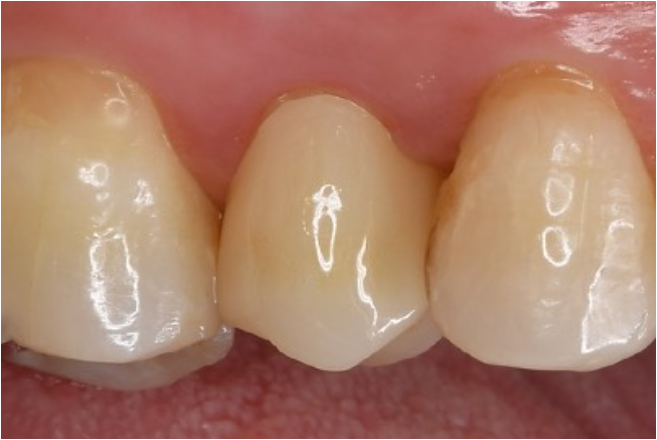

症例2

| 患者様データ | 30代 男性 |

| 来院時の主訴 | 「右上の歯が何もしなくても痛い。他院で神経を取ると言われたが、残せないか相談したい。(セカンドオピニオン)」 |

| 術前検査結果 | 歯髄の生活反応有り、自覚症状有り |

| 医院の診断 | 症候性可逆性歯髄炎 |

| ここがこだわりのポイント!☝ | 術前の症状の強さは神経を残せるかどうかには関係ありません。術前検査情報に加えて、術中のマイクロスコープでの歯髄診査にて神経を残せるかどうかの最終判断を行なっています。 |